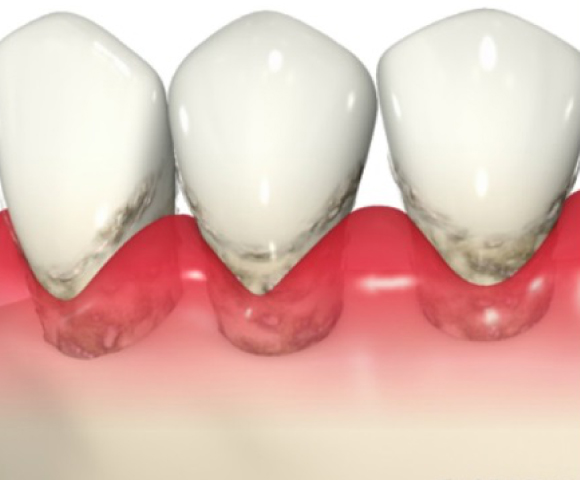

■歯の表面を爪楊枝などで触った時についてくる白いもの。これをプラークと呼びます。これが歯周病の原因です。

■プラークは単なる食べかすではなく細菌の塊(細菌の集合住宅)のようなものです。

■プラークは歯茎の炎症を引き起こし、炎症により歯を支えている骨が溶けてしまいます。

■プラークが固まって歯に頑丈にこびりついたものを歯石といいます。

■歯垢(ばい菌)がたまると歯茎が腫れたり、血が出ます。

■歯茎が腫れると歯を支えている骨が徐々になくなります。

■骨が無くなると歯はぐらぐらになり、食べ物をかめなくなります。

ポケットにプラークや歯石が付着し、歯肉が腫れて炎症をおこしています。

歯石除去と正しいブラッシングにより炎症で腫れていた歯肉が引き締まります。